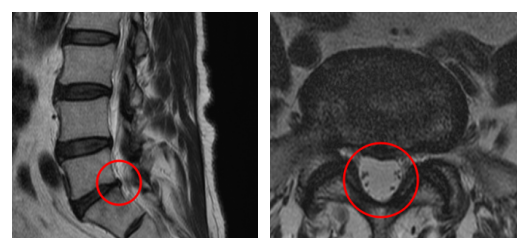

┃検査・診断

赤い枠の部分(L5/S)に強い狭窄を認めました。